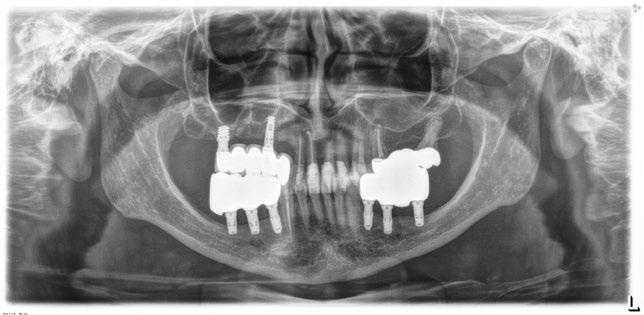

Radiografía final del caso.

Figura 8. En la radiografía inicial ya se hace evidente que los sectores posteriores mandibulares tienen una escasa altura ósea residual y podemos ver desajustes en la prótesis sobre implantes superior del primer cuadrante.

Figura 16. Radiografía de la colocación de los implantes y la prótesis de carga inmediata horas después de la cirugía.

Figura 17. Radiografía final del caso con las prótesis definitivas, tras dos años de seguimiento, sin pérdidas óseas evidentes en ninguno de los implantes estudiados.